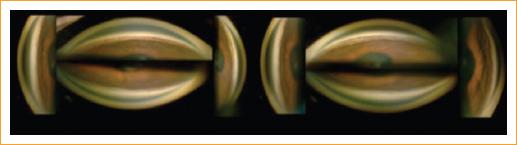

Se sospechó el diagnóstico de probable configuración de iris plateau en el ojo derecho y probable síndrome de iris plateau en el ojo izquierdo, por lo que se solicitó una ultrabiomicroscopia (UBM) de segmento anterior que corroboró el diagnóstico de iris plateau en ambos ojos (Fig. 1).

Figura 1 Ultrabiomicroscopia de ojo derecho y de ojo izquierdo con ausencia del surco ciliar y anterorización de los procesos ciliares.

Es importante mencionar que el diagnóstico de certeza de iris plateau se obtiene mediante UBM, con la cual se observan las características clásicas de este, como son la ausencia del surco ciliar, la presencia de procesos ciliares situados anteriormente que empujan la periferia del iris y la presencia de doble joroba1,2. Así mismo, la UBM permite valorar el eje anteroposterior del cristalino, ya que al estar aumentado puede generar de manera secundaria el empuje de la raíz del iris anteriormente y causar un cierre angular. En nuestra paciente no encontramos dicha característica, pues su eje anteroposterior estaba dentro de parámetros normales (3-6 mm): el ojo derecho con 4.17 mm y el ojo izquierdo con 4.37 mm7. Por ende, no existía ese efecto de empuje del cristalino, y además nuestra paciente no presentó una opacidad del cristalino lo suficientemente densa como para considerar la cirugía de catarata. Retirar un cristalino claro en casos de iris plateau es un tema de gran controversia por el riesgo quirúrgico inherente a la cirugía de catarata.